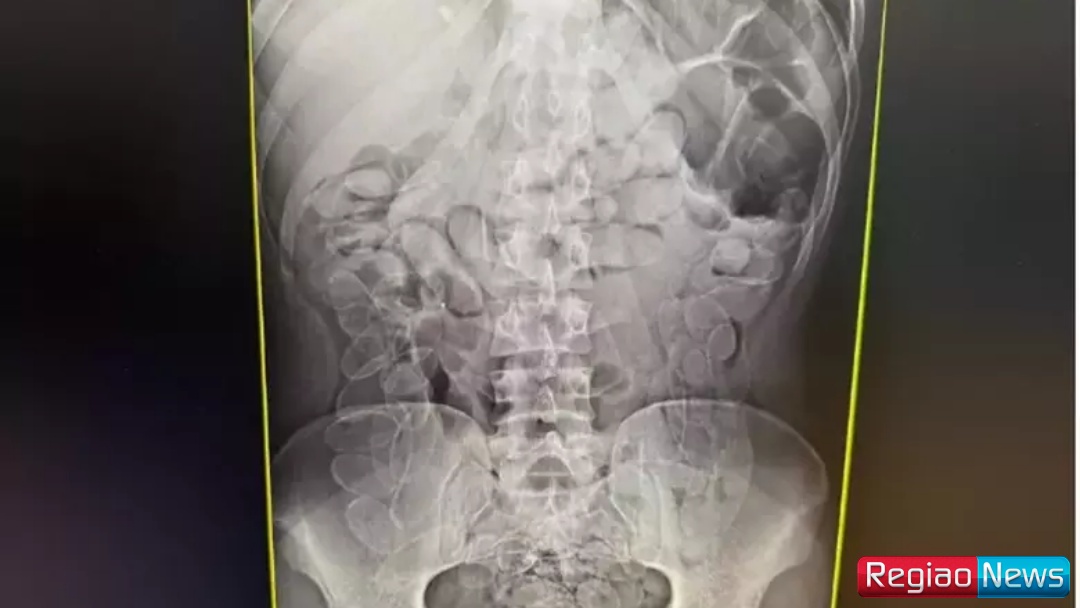

Ainda segundo o boletim de ocorrência, a mulher afirmou ter ingerido as cápsulas em território boliviano há cerca de sete dias e que permaneceu com o material no organismo durante todo esse período. Um exame de raio X da região abdominal revelou múltiplos invólucros no estômago.